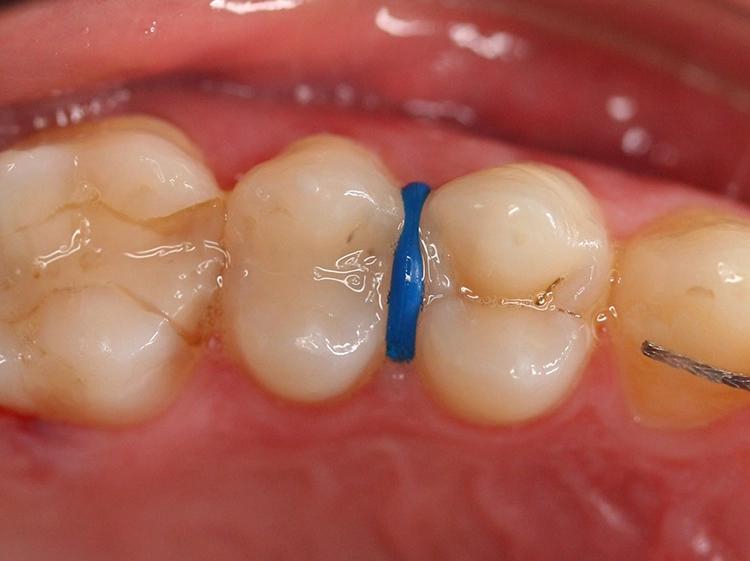

Ein 4-jähriges mäßig kooperatives Kind erscheint zur Kontrolle in der Zahnarztpraxis. Bei der klinischen Untersuchung sind offensichtlich zwei (scheinbar kleinere) approximal kavitierte kariöse Läsionen im Unterkiefer zu sehen sowie Läsionen an den Oberkieferschneidezähnen (Abb. 1a und b). Eine Versorgung dieser Zähne scheint nach klinischer Untersuchung bei diesem Kind noch ambulant möglich.

Direkte klinische Untersuchung bei Approximalkaries Klinisch stellt sich die Diagnostik im Approximalbereich insbesondere von Läsionen in den Stadien ICDAS 1 bis 4 als sehr schwierig dar. Durch die Zahnseparation mit einem KFO-Separiergummi (Abb. 8) und nach dessen Entfernung etwa 1–3 Tage später ist klinisch jedoch eine direkte visuell-taktile Untersuchung der Approximalfläche möglich.

Nachteilig ist jedoch die Notwendigkeit eines zweiten Termins. Mitunter kann dies durch geübte Untersucher umgangen werden, denn nach etwa 2 Stunden Wartezeit nach Applikation ist eine sehr kurze direkte Untersuchung direkt nach Entfernung des Gummis möglich.

Dr. J. SchmoeckelAbb. 8: Die Zahnseparation mit einem orthodontischen Separiergummi ermöglicht eine direkte klinische Untersuchung der Approximalflächen nach dessen Entfernung.